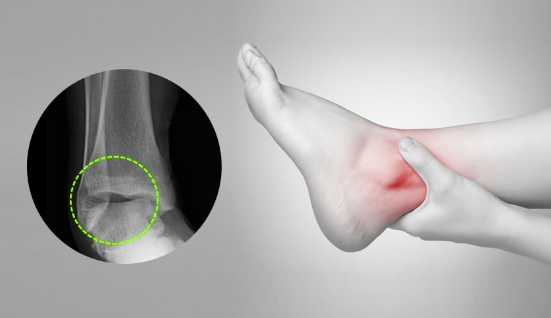

3. 골절

발목 골절은 발목 뼈 중 하나 이상이 부러진 경우를 말합니다. 이는 추락, 사고 또는 스포츠 부상과 같은 다양한 이유로 발생할 수 있습니다.

치료 방법 :

- 캐스트, 스플린트 또는 브레이스로 고정합니다.

- 일부 경우에는 부러진 뼈를 다시 정렬하고 안정화하기 위해 수술이 필요할 수 있습니다.

- 힘과 기동성을 되찾기 위한 물리 치료가 필요할 수 있습니다.